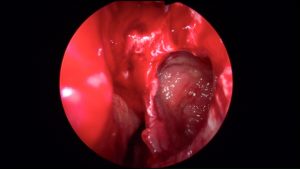

The patient’s with sinus problems are encouraged to follow up with our doctors to have more thorough examination. The physical examination may also include an office endoscopy to assess the patency of the sinus drainage pathways. Occasionally, a CT scan of the nasal sinuses might be necessary to better delineate the extent of the patency.